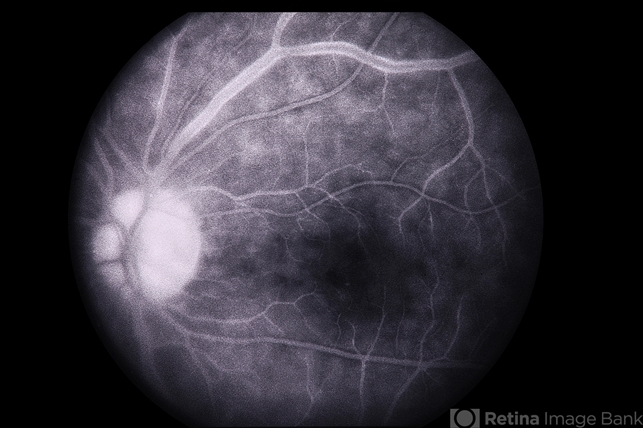

- Behcets

- Behcet's Disease

- Korean male with unilateral vasculitis / mouth ulcers.